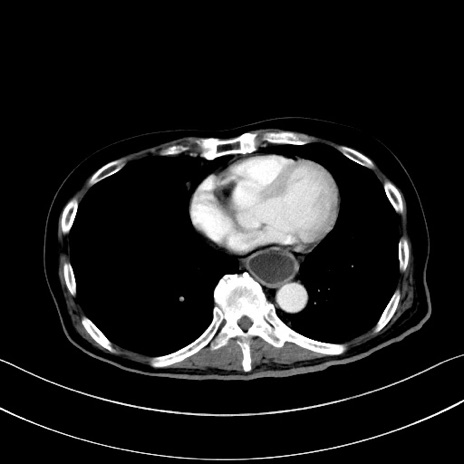

症例28(横断像)

【症例】60歳代男性

【現病歴】胃癌にて胃全摘後。食思不振が悪化し、夜中に嘔吐することがある。

【既往歴】胃癌、胃全摘、脾摘、胆摘後

【データ】WBC 5900、CRP 10.56